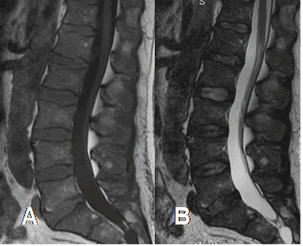

Fig 12 A. Reconversión de medula ósea, por neoplasia de colon.

A: RM sagital en T1 y B: RM sagital en T2. Disminución en la SI de las vértebras, por predominio de la MO roja, como estímulo a cuadro anémico.